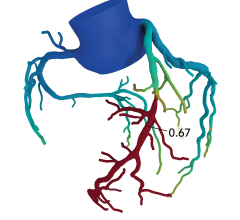

December 15, 2022 — An accepted manuscript published in ARRS’ American Journal of Roentgenology (AJR) guides ...